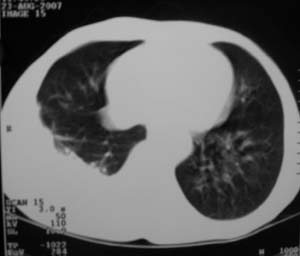

男,54岁,无任何不是感.体检发现右肺部阴影.现行ct进一步确诊.

右侧胸廓塌陷,肋间隙变窄,肋骨增生变粗,脏壁层胸膜肥厚、钙化。符合陈旧性结核性脓胸改变

右侧包裹性积液伴胸膜钙化.

右侧包裹性积液并胸膜钙化,性质还是结合穿刺细胞学检查的好,结核性、化脓性均会有钙化。

右测包裹性积液并胸膜钙化,结核性脓胸还是胸膜肿瘤转移,还需要穿刺抽液

包裹性积液伴胸膜钙化,原因多种,国民一般为结核性居多